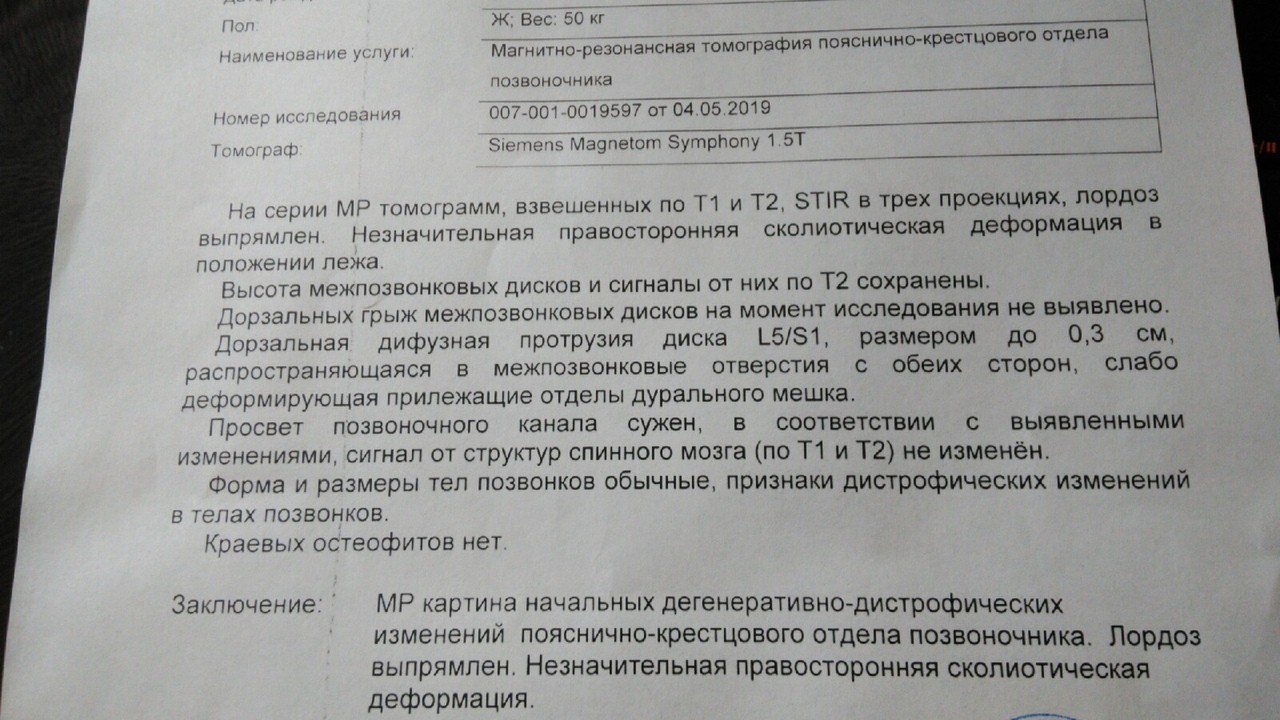

Мрт картина дегенеративно дистрофических изменений пояснично крестцового отдела позвоночника